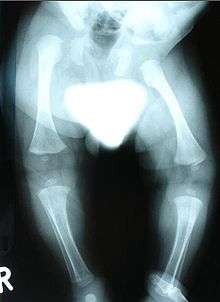

Radiograph showing dysplasia in lower limbs